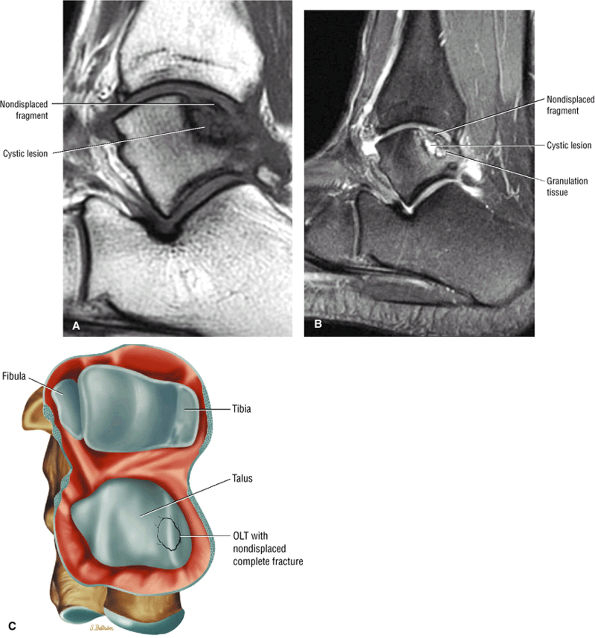

Stage I: Subchondral trabecular compression. Radiograph results are negative, bone scans are posi-tive, and marrow edema is seen on MR imaging (Fig. 5.95).

Stage IIA: A subchondral cyst (Fig. 5.96)

Stage IIB: Incomplete separation of the fragment (Fig. 5.97)

Stage III: Fluid around a nondetached, nondisplaced fragment (Figs. 5.98 and 5.99)

Stage IV: A displaced fragment (Fig. 5.100)

FIGURE 5.98 ● Stage III OLT with fragment adherent to granulation tissue but separated from the overlying chondral surface, (A) Coronal section color graphic. (B) Coronal T1-weighted image. (C) Coronal FS PD FSE image.

FIGURE 5.99 ● Nondisplaced fragment in a stage III OLT with intermediate-signal-intensity granulation tissue at the fragment—talus interface. (A) Sagittal T1-weighted image. (B) Sagittal FS PD FSE image. (C) Color graphic with superior view of talus.